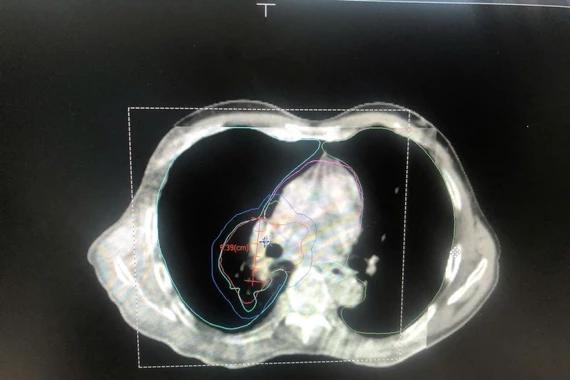

Bệnh nhân C.V.Q (nam, 61 tuổi) nhập viện vì tiêu phân đen, tiền căn ung thư tâm vị dạ dày giai đoạn T4N2M1, di căn phổi – gan – xương (phát hiện từ tháng 6/2025). Bệnh nhân hóa trị được 01 tháng thì ngưng điều trị, sau đó tiếp tục nhập viện và đến nay đã hóa trị đến chu kỳ 4 (FOLFIRI).

Trong quá trình nhập viện, bệnh nhân tiêu phân đen tăng dần, HGB ghi nhận giảm từ 7 -> 3.3 g/dl, BN được chỉ định truyền máu và nội soi dạ dày ghi nhận: sang thương chồi sùi, chiếm hết chu vi chỗ nối thực quản - dạ dày gây hẹp lòng, máy soi không qua được, mô bở, dễ chảy máu, ống soi không tiến xa được thêm.

Kết hợp thăm khám đánh giá, đây là một trường hợp biến chứng xuất huyết nặng do ung thư tâm vị có thể dẫn đến sốc mất máu suy đa cơ quan. Các bác sĩ hội chẩn đã quyết định tiến hành can thiệp cấp cứu tắc mạch khối u dạ dày cầm máu.